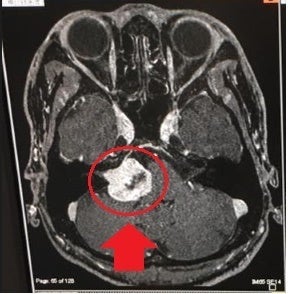

ところが、23歳の若さで自分が

脳腫瘍に侵されていると判明し

25歳のとき、脳腫瘍摘出手術を行いました。

誰が見てもわかる脳腫瘍がありました

腫瘍の97%は摘出でき、手術は成功。